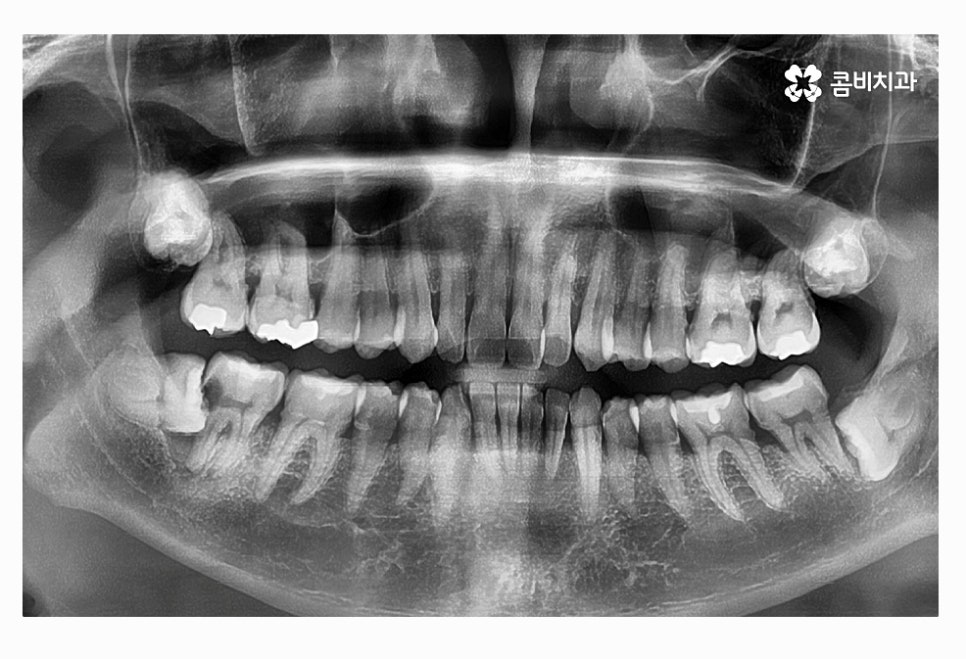

위 사진에서 보시는 것처럼 사랑니가 누워서 자라는 사례는

턱뼈가 좁은 한국인들에게 자주 나타나는 사례이며

음식물이 치아 사이에 끼거나 치석이 쌓이기 쉽기 때문에

청결 관리 미흡으로 인한 구강질환이 발생할 수 있어요.